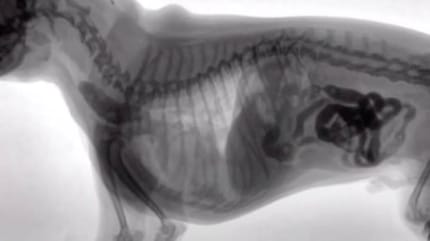

Con quello che c'era nello stomaco del cagnolino, si poteva riempire uno scaffale di biancheria intima femminile: mutandine sgambate, minuscoli perizoma e tanga filiformi, o almeno quello che ne restava.

A quanto pare le mutande vanno per la maggiore tra gli oggetti più strani ingurgitati dai cani. Ma il colmo è stato ritrovare un vibratore nello stomaco di uno di loro!